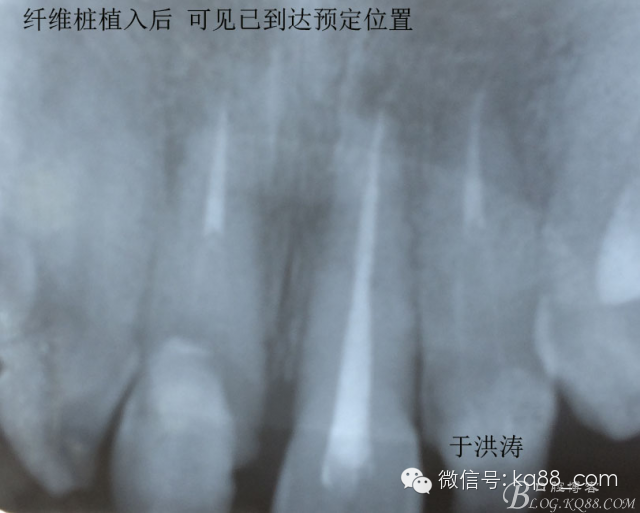

檢查:明顯可見22牙冠橫向斷裂至頸1/3處,近遠中與腭側斷裂至齦下??梢?/span>11牙冠斜向近中斷裂,近中與腭側均斷裂至齦下。21牙冠中1/3有裂痕。11 21 22松動(0),11 21叩(+),22叩(-),11 21 22探(-),11 21 22冷熱(-)。11 21 22唇側牙齦與粘膜和根尖相應部位未見明顯改變。11 22腭側牙齦增生性改變。11 21 22腭側粘膜和根尖相應部位未見改變。11 21 22舌側窩均有充填物。面部左右對稱無改變。余牙正常。(11,21,22牙冠顏色無改變)。 輔助檢查:X線片檢查11 22牙冠均有缺失。11 21 22 髓腔內均有充填物,11充填不到位, 21充填不實,22充填到位髓腔高密度影像。11 21 牙周膜有增寬,21根尖區(qū)有2mm左右低密度影像。未發(fā)現(xiàn)有牙根側穿或斷裂異物。 診斷:11,21慢性尖周炎,11,22殘冠。 治療計劃: 22無需治療。11 21 建議牙齒根管再治療。告知情況及費用。 1,11 21去除根充物。 2,11 21根管治療。 3,11 22纖維樁樹脂核修復。 4,高頻電刀去除11 22腭側牙齦組織到斷面。 5,11,21,22全瓷單冠修復牙齒。 治療過程:經(jīng)患者同意。H銼去除11 21原有充填物,未發(fā)現(xiàn)明顯滲出物,無異味。K銼疏通根管,VDW根測儀測量長度,11牙20mmWL,21牙20mmWL。S3鎳鈦器械預備根管。(全程1%次氯酸鈉沖洗EDTA溶解潤滑)試尖片顯示牙膠未到位,繼續(xù)向牙根尖各2mm進入預備。吸潮紙尖吸干根管,登士柏樹脂根充糊劑輸送至根尖部位,以測量數(shù)據(jù)用牙膠尖冷充側壓充填根管,3M玻璃離子封閉根管口。不可用患牙啃咬硬物,擇日冠修復。 輔助檢查:插針X線片顯示根管內充填物已經(jīng)取出。試尖片顯示牙膠尖未到位,繼續(xù)用K銼和機括向根尖預備。根充結束片顯示根充密實,無超充,無欠充。 醫(yī)囑:常規(guī)醫(yī)囑,不適隨診。 各步驟操作見下圖 于洪濤 2015.02.03 復 診 主訴:無疼痛,不適癥狀已經(jīng)消失。 檢查:11 21 充填物存在邊緣封閉完好,叩(-)松動(0)牙齦及周圍同初診。11 21 22無任何不適。 治療過程:由于患者自身原因即將兩個月來復診。拍X線片,去除11 22髓腔內部分牙膠,P鉆預備根管到達預定位置。粘結纖維樁,制作冠核。初預備11 21 22牙冠。高頻電刀按廠家要求功率和方法去除11 22腭側牙齦組織到達牙齒斷裂部位,調整檔位和功率繼續(xù)凝固和精修腭側組織,11 21 22排齦精修拋光。硅橡膠兩次法取模,可見模型完整肩臺清晰。制作臨時冠,科爾不含丁香油臨時冠粘結系統(tǒng)粘接。 模型送技師制作。預約義齒佩戴時間。(需術前牙齒比色) 輔助檢查:X線片顯示根尖低密度影像消失,牙周未見異常。X線片顯示纖維樁密合到位。 醫(yī)囑:不可用臨時牙肯咬硬物,不適隨診。 各步驟操作見下圖 于洪濤 2015.03.26 復 診 主訴:牙齒無癥狀,自感腭側術區(qū)舌舔粘膜不適。 檢查:臨時冠完整,無松動,邊緣緊密。牙齒無疼痛,唇側牙齦無明顯紅腫,腭側牙齦愈合良好,牙冠肩臺邊緣清晰。腭側牙齦術區(qū)中度觸及有少量滲血。 治療過程:義齒制作完成。去除臨時冠及粘結物。義齒試戴調整完全就位,無懸突,無縫隙。清洗義齒,氫氟酸處理義齒50秒(加強醫(yī)患防護),沖洗吹干,偶聯(lián)劑處理備用。基牙37%酸處理15秒,沖洗吹干,隔濕,排齦,涂第五代粘結劑。小蜜蜂雙固化樹脂水門汀激活攪拌注入義齒中,按順序就位,加壓力,牙線去除牙縫隙多余樹脂,涂阻氧劑,基牙唇腭側各光照固化3秒之后去除多余水門汀取出排齦線,繼續(xù)光照固化牙齒每個面20秒。精細查找去除多余水門汀。 醫(yī)囑:1,患牙咀嚼硬物加以注意。 2,常規(guī)醫(yī)囑,不適隨診,。 3,加強口腔衛(wèi)生意識。定期復診檢查。 各步驟操作見下圖 于洪濤 2015.04.07 回訪病例 主訴:咀嚼食物非常自如,無任何不適。 檢查:義齒牙體完整。無松動,無叩痛。唇側牙齦紅潤質韌無萎縮,腭側術區(qū)牙齦愈合良好,無炎癥改變。唇腭側根尖相應部組織無改變。余牙正常。 輔助檢查:X線片顯示牙根及周圍未見異常。未見骨萎縮。牙冠及頸部未見異常。 醫(yī)囑:定期檢查義齒,不適隨診。 各步驟操作見下圖 于洪濤2015.04.28